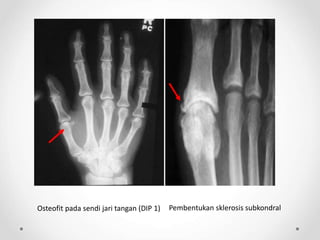

OA pada jari tangan OA pada jari kaki

Gambaran radiologis posteroanterior menunjukkan penyempitan ruang sendi

interphalangeal, sklerosis subchondral, dan pembentukan osteofit (panah)

Sumber : Jacobson, JA, et al. 2008. Radiographic Evaluation of Arthritis : Degenerative Joint Disease and Variation. Radiology. 248(3) : 737-747.

Osteofit pada sendi jari tangan (DIP 1) Pembentukan sklerosis subkondral